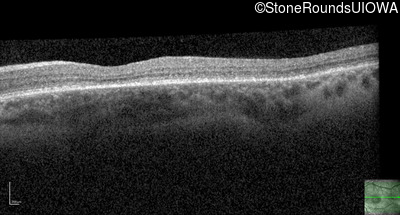

Optical Coherence Tomography - Left - 20/200 +2

Exemplar / OCT Stack

OCT Stack